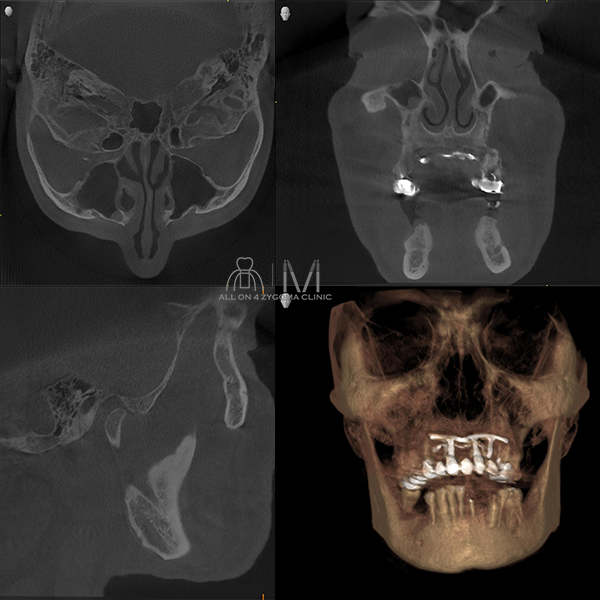

術前CT画像所見

上顎前歯相当部にはブレードインプラントを認める。インプラント周囲に炎症を示唆する明らかな所見は認めない。下顎骨は骨硬化を認める。 両側頬骨の骨幅は十分な幅を認める。 両側上顎洞に明らかな病変は認めない。

上顎前歯部はブレードインプラントを除去する事で骨のボリュームが更に少なくなる、また両側上顎臼歯歯槽骨に十分なボリュームがないため、両側臼歯部のザイゴマインプラント4本埋入を検討した。下顎は全体的に十分な骨幅があり、歯槽頂部から下顎管までの十分な骨幅を認める為、十分な骨整形を行い、安定度を高めるプラットフォームの設計が必要であると考えた。術中は静脈内鎮静法下での手術を予定した。